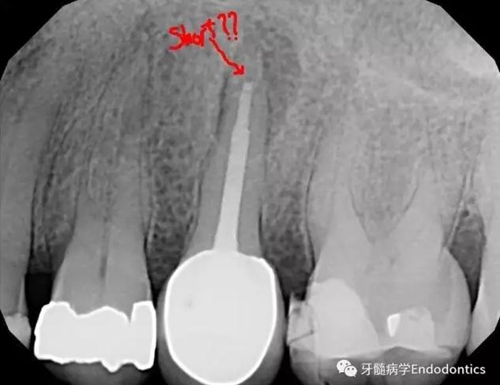

圖1.術(shù)前X線(xiàn)片示#25根管治療完善,根尖周?chē)竺娣e病變

圖3.術(shù)后X線(xiàn)片示根充物距離根尖有3mm的距離